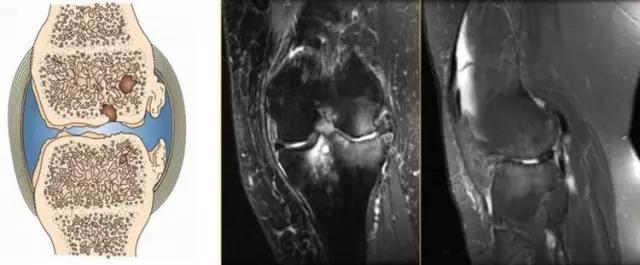

地中海贫血与白血病均为血液系统的问题,主要表现在骨髓,疾病的发病机理有别,MRI表现也不相同;我们可能不是很熟悉这些疾病,也能够从MRI发现区别。图1:正常膝关节 图2:地中海贫血 图3:白血病

利用自身对比——

我们可能都不熟悉T1、T2,怎么办?当我们发现有问题后,利用照片上图像的对比,推测病变的可能也是一种诊断方法。病例:黄XX,女,39岁,左膝关节反复交锁1年。图1:肿物信号与骨信号一样图2:肿物信号与骨信号一样图3:肿物信号与骨信号不一样 肿物应该与骨相关,但不是骨性,推断:膝关节滑膜软骨瘤。手术后得到证实。